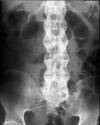

Describe this fracture?

A

CHANCE

- Vertebral fracture, usually lumbar, involving the posterior spinous process, pedicles, and vertebral body

- simultaneous flexion and distraction forces on the spinal column, usually associated with use of lap seat belts; anterior column fails in tension, along with the middle and posterior columns; may be misdiagnosed as a compression fracture